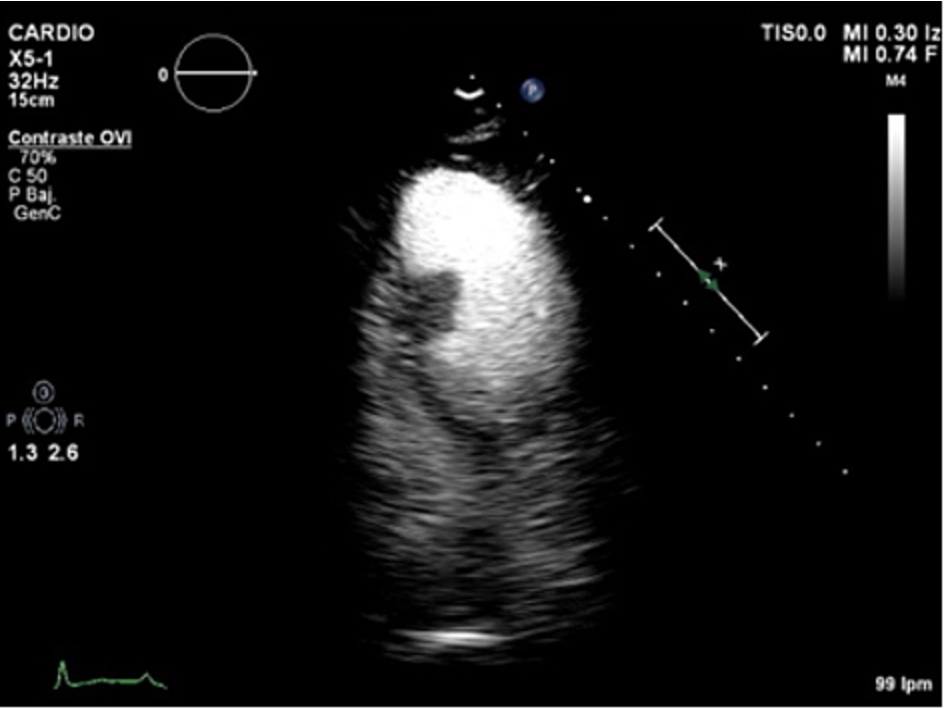

Apical four-chamber echocardiographic view. Left ventricular mass attached to inferior interventricular septum.

Echo-contrast was administered, showing perfusion of the mass, excluding the diagnosis of thrombus.

Conventional transthoracic echocardiography was repeated a week later, without changes. 2D-echocardiographic study was completed with intravenous echocardiographic contrast to demonstrate perfusion of the mass, excluding the diagnosis of thrombus (Movie II in the Data supplement) and with 3D echocardiography for better visualization and establishing spatial relationships of the mass (Movie III and Movie IV in the data supplement).